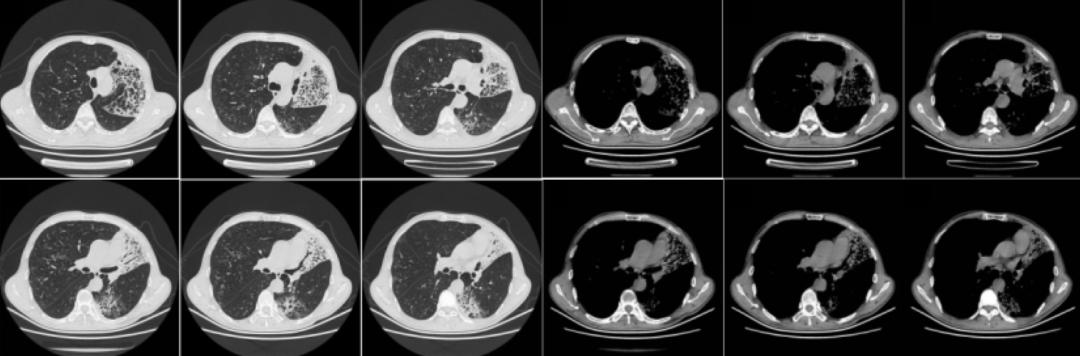

2019年3月13日,距离该患上一次住院时隔一年之后,其再次「因胸闷、气短1年余,加重1周」之主诉来我院就诊。以下为其2019年3月12日胸部CT的影像学资料:

胸部CT提示两肺间质性改变并右肺中上叶及左肺炎症,较前增多(2018年10月11日);肺气肿伴肺大泡形成;右肺中叶及两肺下叶结节,较前片变化不著;左侧胸膜增厚。

2019年3月12日:

对比以上这些胸部CT,提示左肺上叶实变影变大,呈蜂窝状,左肺下叶出现磨玻璃影及少许蜂窝影。此时我们考虑患者胸部CT表现的蜂房影、囊腔影是细支气管阻塞的征像,左肺下叶磨玻璃影考虑气性播散,临床高度怀疑肺癌。